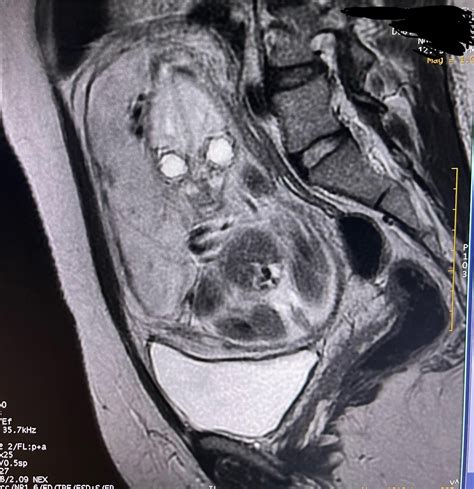

• Magnetic Resonance Imaging (MRI): Uses magnetic fields and radio waves to produce detailed images. MRI is generally safe during pregnancy, although contrast agents should be avoided unless absolutely necessary.

After a CT scan while pregnant, it is essential to monitor the pregnancy closely. Regular prenatal check-ups and ultrasounds can help ensure the health and development of the fetus. If there are any concerns or unusual symptoms, it is crucial to inform the healthcare provider immediately.